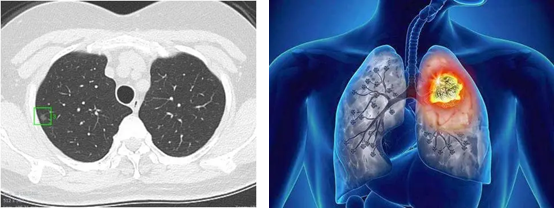

平常老讲肺结节,到底什么是肺结节,这是个概念的问题,就如图中这张胸部CT,就是这个肺上长了个小阴影,更准确的说就是肺部CT上看到的非正常阴影,我们把肺内小于3厘米的占位性病灶叫结节,大于3厘米的叫肿块。肺结节又再细分为纯磨玻璃结节、混合磨玻璃结节以及实性结节。其中以混合磨玻璃结节最可能为恶性。结节可以是圆形类圆形,也可三角形或不规则形,甚至有些呈小片状。多数长在肺的外周部位,有时也会靠肺叶中央,一般较少位于紧邻主支气管的中央型。总的来讲,肺结节可以是肺癌,肺部感染,肺部良性肿瘤,等等,所以说肺结节不一定肿瘤,相对来讲肺结节是肺癌的概率还是较低的,当然,判断肺结节性质的事还是交给专业医生吧!